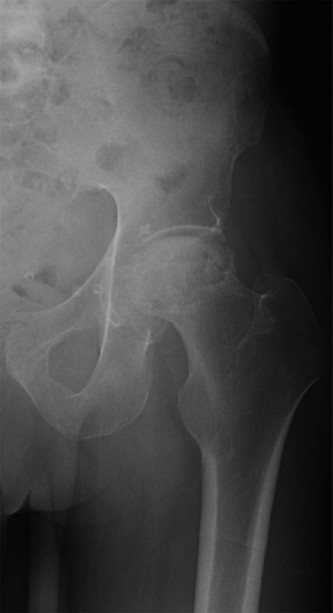

An 82-year-old woman, with a BMI of 33.9 and history of total hip replacement performed 8 years ago, sustaine…